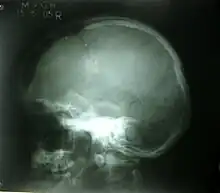

| Skull fracture | |

| A piece of a skull with a depressed skull fracture | |